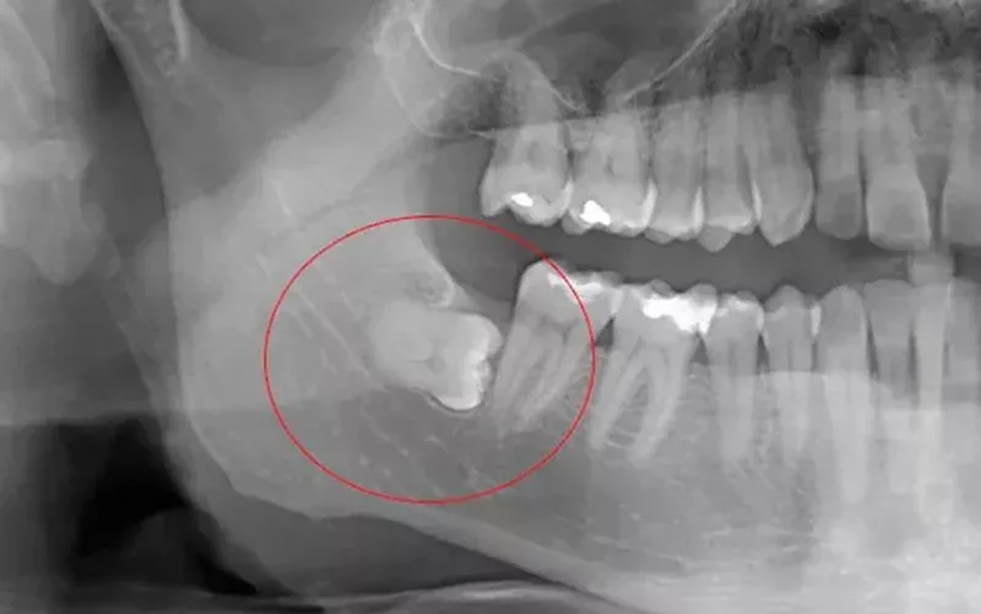

В государственную стоматологическую поликлинику центра одного из северных регионов РФ обратилась 33-летняя женщина, у которой после обследования был диагностирован непрорезавшийся (вследствие врождённого атипичного расположения в зубной лунке нижней челюсти) зуб мудрости с хроническим воспалением окружающих мягких тканей. Лечение данной патологии заключается в хирургическом удалении зуба после резекции (раскрытия) костной лунки челюсти и предварительного дробления его бормашиной, что и было произведено больной. В раннем послеоперационном периоде лечащий врач стоматолог-хирург, не проведя обязательное контрольное рентгенисследование, обрабатывал операционное поле антисептиками и назначал медикаментозное лечение. Через неделю во время жевания пищи пациентка почувствовала и услышала треск в месте операции на нижней челюсти. При посещении пациентки поликлиники лечащий врач провёл рентгенисследование, но не только не описал снимок, но и вообще не упомянул о процедуре. При этом он продолжал